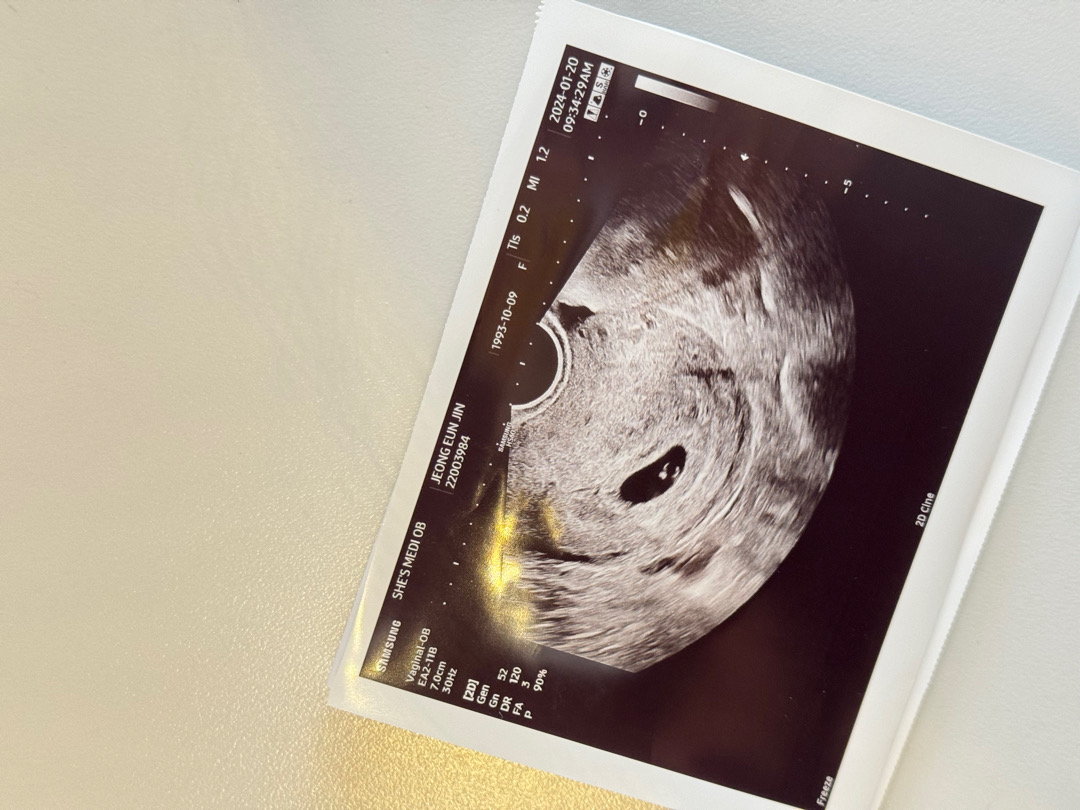

6주 아기 보러갔다가

다이아몬드 반지 보고왔어요 세상 예뻐요🤍😀

다이아몬드 반지.. 너무 이뻐요...!!!!!!!! 저렇게 선명하게 나오다니!!!